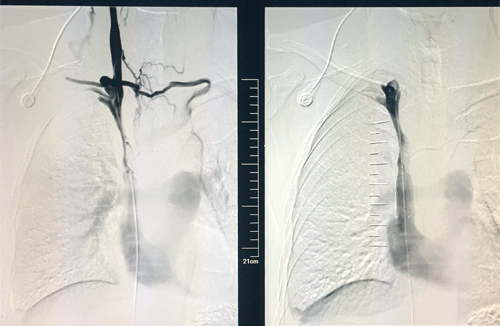

48岁的章先生近期因咳嗽、胸闷入临床医学院/附属医院就诊,不幸确诊为肺癌晚期,伴上腔静脉重度狭窄,逐渐出现颜面部及上肢浮肿,胸壁浅表静脉扩张,并有显著胸闷及颜面部肿胀。为提高患者生活质量,延长患者生存期,该院呼吸内一科介入组决定为其实行上腔静脉支架置入,经术前充分评估,术中精细操作,以20分钟完成支架置入。术后,上腔静脉再通,胸壁“蚯蚓”消失,症状瞬间缓解,达到立竿见影的治疗效果,赢得患者及家属的高度称赞。